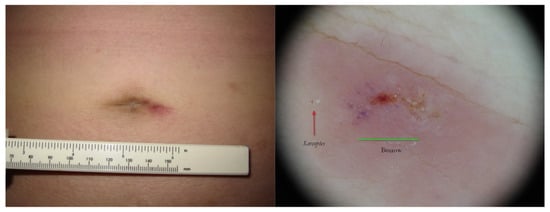

Figure 3.

Post-therapy non-specific lesion under buttock after two 5% Permethrin applications 7 days apart (left). Under wet dermoscopy, inside erosion, there was an unexpected MGU with the delta sign of Sarcoptes (A) and a gallery with fecal pellets (B) that faded in a fuzzy tail (C). All around, there was a purplish area (D) corresponding to superficial hematoma caused by patient scratching (right). A yellow highlighter was used.

Figure 4.

The same lesion under UVA light showed a linear white luminescence (left, red box). In full-frame vision (right), it was possible to distinguish a Mite-Gallery Unit whose head part was occupied by Sarcoptes, which featured a green hue (green dot). Between body and tail MGU, there was a luminescent cloud caused by exudate and phlogosis around burrow (rocket sign). A yellow highlighter was used.